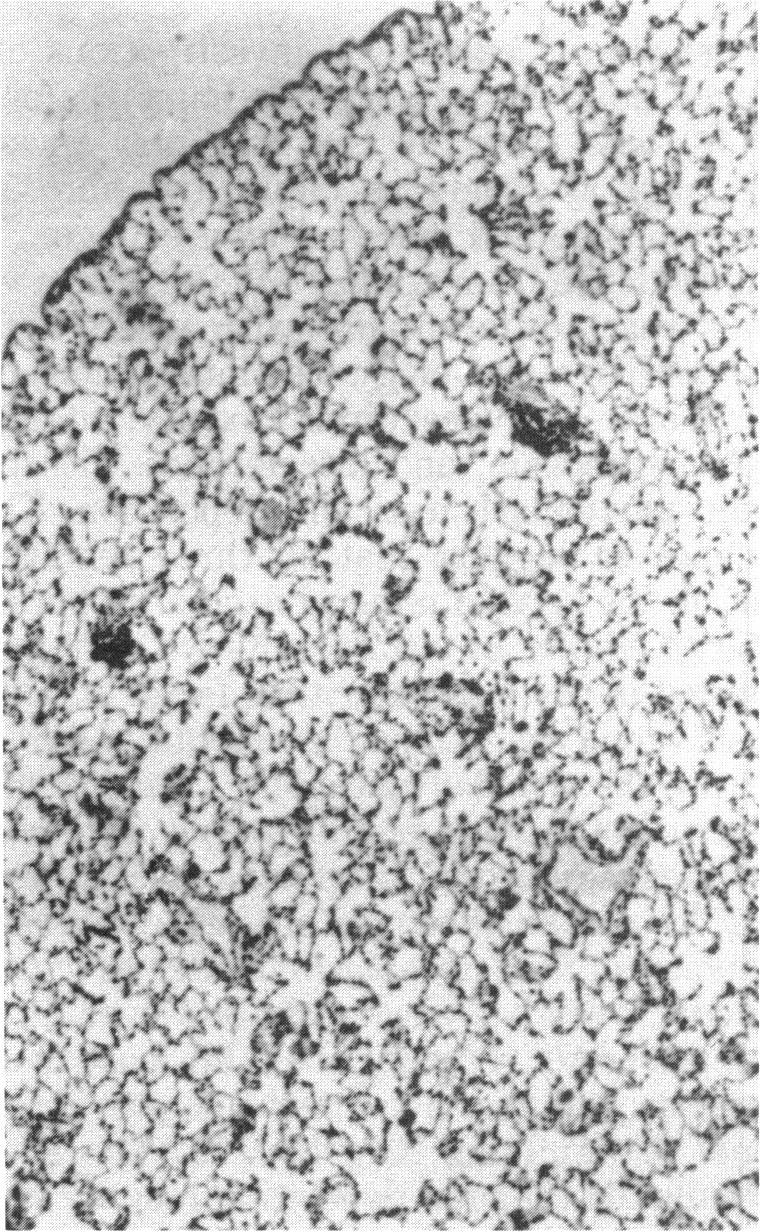

The sequence of cellular and biochemical events in response to the deposition of dust particles in lung tissue is described. Primary reactions at the lung surface include changes in the free cell population, the alveolar surface protein and in the quantity of pulmonary surfactant, a lipoprotein-rich material secreted by Type II cells. The relationship between these changes and lung fibrogenesis is discussed. It is suggested that such primary changes are protective mechanisms which may assist in the prevention of fibrogenesis rather than lead to an increase in collagen formation and deposition. If these primary defenses are overcome, then the interstitial fibroblastlike cell may have a prominent role in fibrogenesis. Therefore detailed observations of the interaction between lung fibroblasts and mineral dusts in vitro are described. As fibrogenesis may be arrested in vivo, or possibly reversed, and does not always progress to fibrosis, final consideration is given to the step from fibrogenesis to fibrosis. It is suggested that this step may involve other tissue proteins apart from collagen and that the irreversible nature of fibrosis can be explained by the formation of strong intermolecular crosslinks between different proteins. The types of crosslinks that may be involved are discussed. Emphasis is placed on the role of calcium-dependent transglutaminases in fibrosis, as these enzymes have hitherto received little attention.